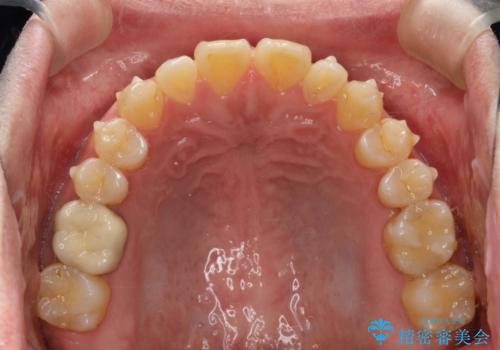

前歯の隙間 インビザラインにて整った歯並びへ

- 前歯の隙間が気になるとのことで来院されました。

インビザラインにて矯正治療を行うこととしました。

下の歯と歯の間にわずかに隙間をつくり、上の前歯の隙間を閉じました。